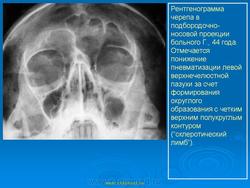

На верхней челюсти кисты встречаются в 2 раза чаще, чем на нижней. Кисты от верхних центральных резцов и клыков могут расти в сторону полости носа — при этом образуется выпячивание в полость нижнего носового хода или под нижнюю носовую раковину (симптом Gerber). Иногда может отмечаться рост в сторону твердого нёба, в этом случае на твердом нёбе появляется полушаровидное вздутие. Если рост кисты происходит в сторону верхнечелюстного синуса, наружных проявлений долгое время не отмечается. Диагноз в этом случае обычно ставится при нагноении кисты, проявлении симптомов периостита и синусита и на основе данных рентгенографии. Также на верхней челюсти может отмечаться рост кисты в сторону преддверия рта, при этом отмечается выбухание и деформация альвеолярного отростка.

При подозрении на наличие радикулярной кисты необходимо провести рентгенологическое исследование: ортопантомограмму или панорамную рентгенографию, прицельный снимок причинного зуба, по показаниям — рентгенографию придаточных пазух носа. На рентгенограмме отмечается тень округлой или овальной формы с четкими границами, связанная с верхушкой зуба. Непрерывность компактного слоя альвеолы в области верхушки «причинного зуба» нарушена. Динамика радикулярных кист может осложняться синуситом и переломом. Однако наиболее часто происходит нагноение кист.

Если воспаление кисты острое, то процесс протекает по типу острого периостита. Однако нередки случаи, когда изначально воспалительный процесс носит хронический характер. При этом часто наблюдается образование свища на десне с периодическим гнойным отделяемым. Кисты, стенка которых на большом протяжении соприкасается со слизистой оболочкой верхнечелюстного синуса, могут вызывать хронический полипозный синусит, также с периодическими обострениями.